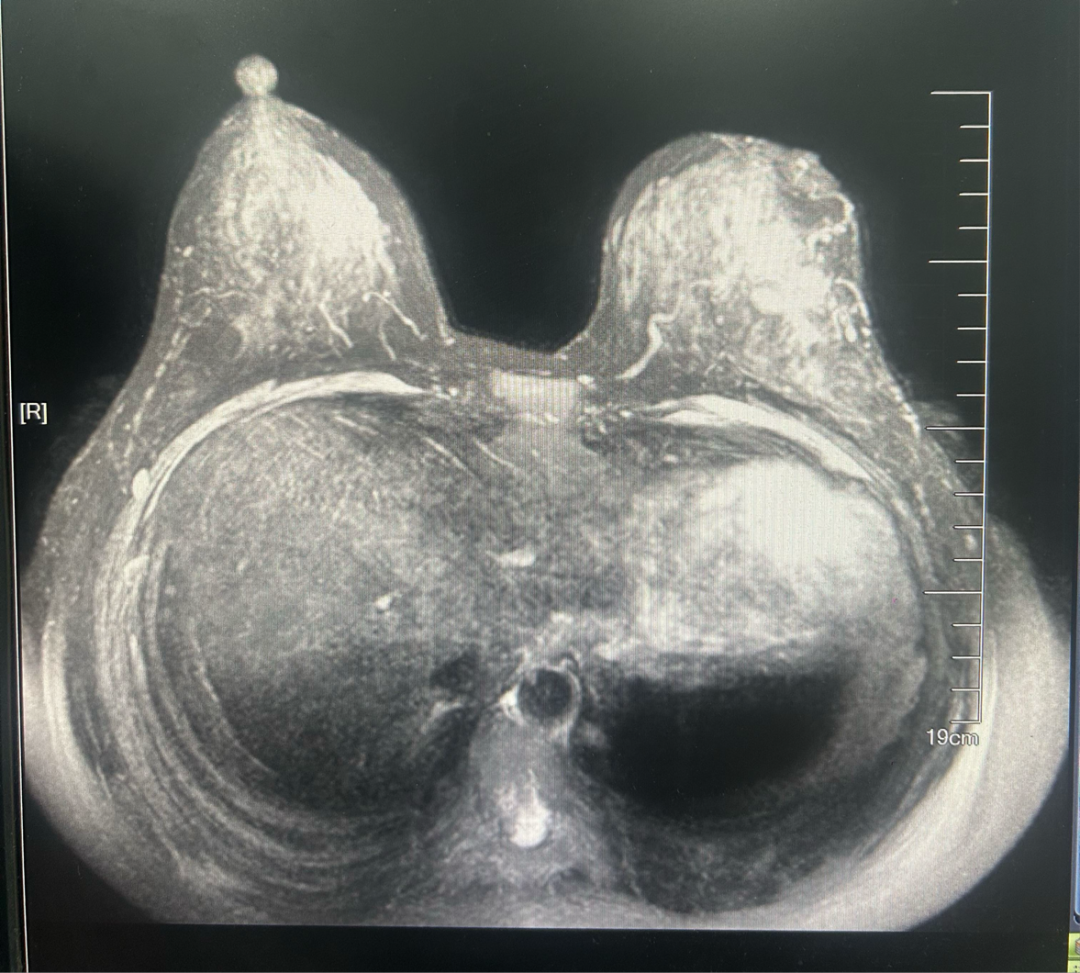

·乳腺MR

图2.2023年6月28日乳腺MR结果

1、左乳外下象限肿块,考虑恶性。(BI-RADS 5)

2、左侧乳头凹陷并强化,左乳下份皮肤结节样强化,请结合临床及其他检查。

3、右乳外份条带样异常信号,硬化性腺病与其他待鉴别,必要时活检。(BI-RADS 4A)

4、双乳多发点结状强化灶。(BI-RADS 3)